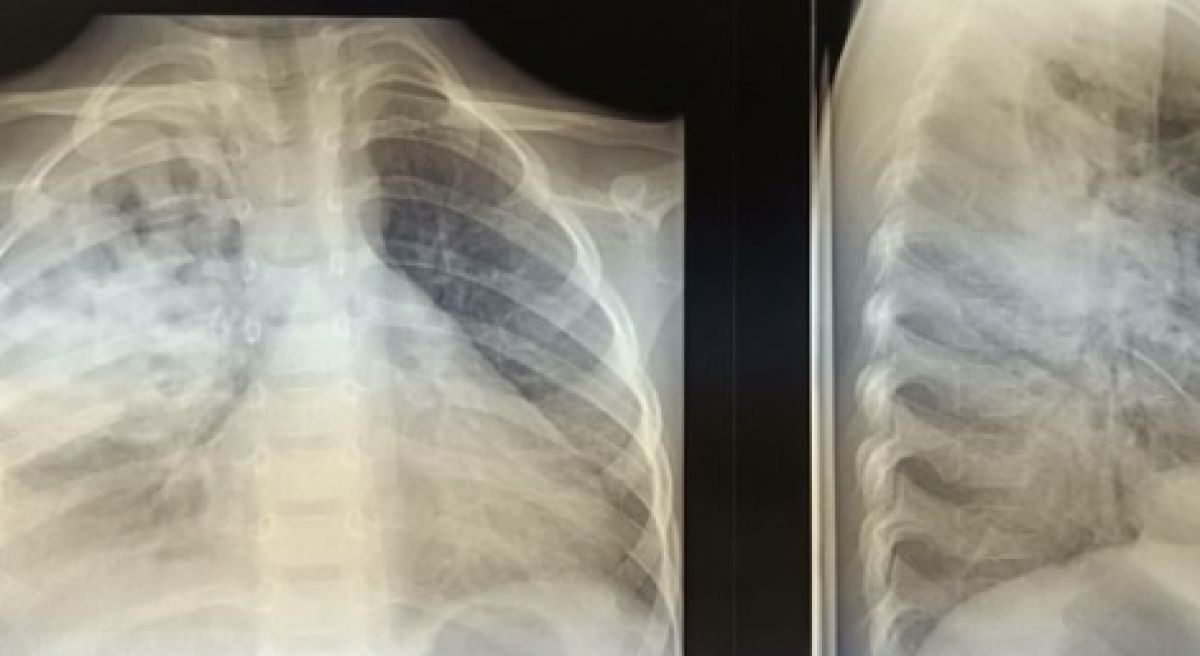

Владимирские врачи вылечили ребенка от тяжелой формы гнойной пневмонии Врачи-педиатры смогли поставить на ноги ребенка с тяжелой формы пневмонии со скоплением гноя и воздуха в плевральной полости,

Врачи-педиатры смогли поставить на ноги ребенка с тяжелой формы пневмонии со скоплением гноя и воздуха в плевральной полости, рассказали в областной детской клинической больнице.

По словам медиков, потребовалось проведение дренирования плевральной полости. Затем юному пациенту назначили физиотерапию и подобрали терапию. В настоящее время малыш уже выписан домой.

Врачи также добавили, в раннем возрасте смертность от данного заболевания относительно высока.